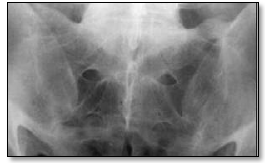

De acordo com os critérios modificados de Nova York, como seria classificada a seguinte radiografia de sacroilíacas?